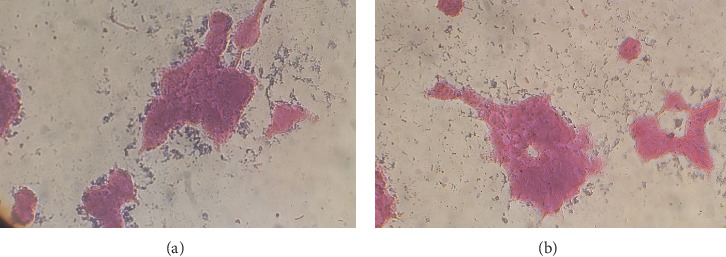

Abstract Image